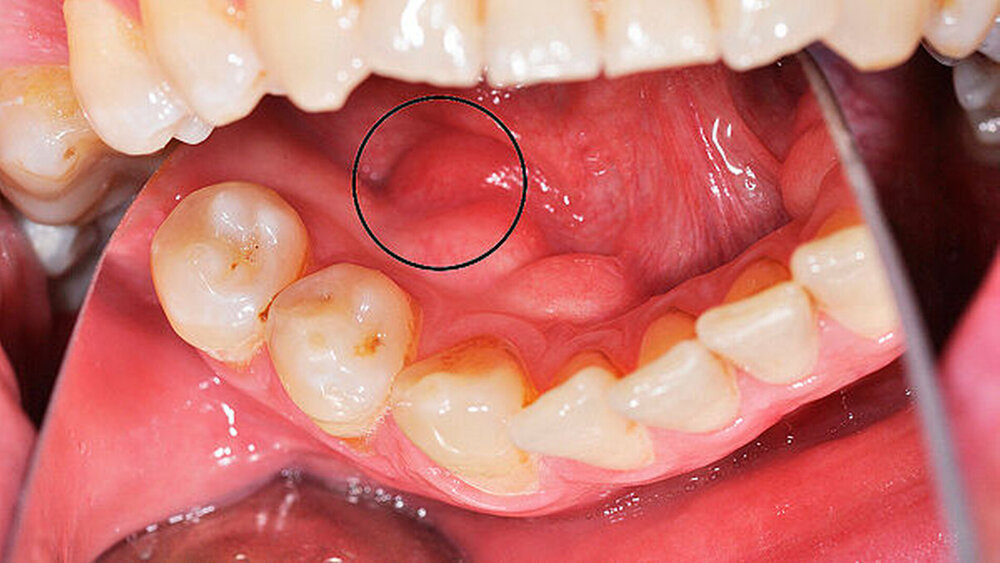

Im Rahmen der klinischen Erstuntersuchung fiel eine kleine, tastbare, nicht druckdolente Raumforderung im Bereich des Mundbodens links mit enger Lagebeziehung zu einem Torus mandibularis (Abbildung 1) auf. Es bestanden keine Einschränkungen der lingualen Mobilität oder der Sensibilität. Die Sprache war nicht beeinträchtigt. Die sonografische Untersuchung zeigte eine 12 mm x 12 mm große, echoreiche, inhomogene Raumforderung im Bereich des Mundbodens regio 34 direkt lingual des Unterkiefer- knochens (Abbildung 2) sowie zahlreiche am ehesten reaktiv vergrößerte Lymphknoten.